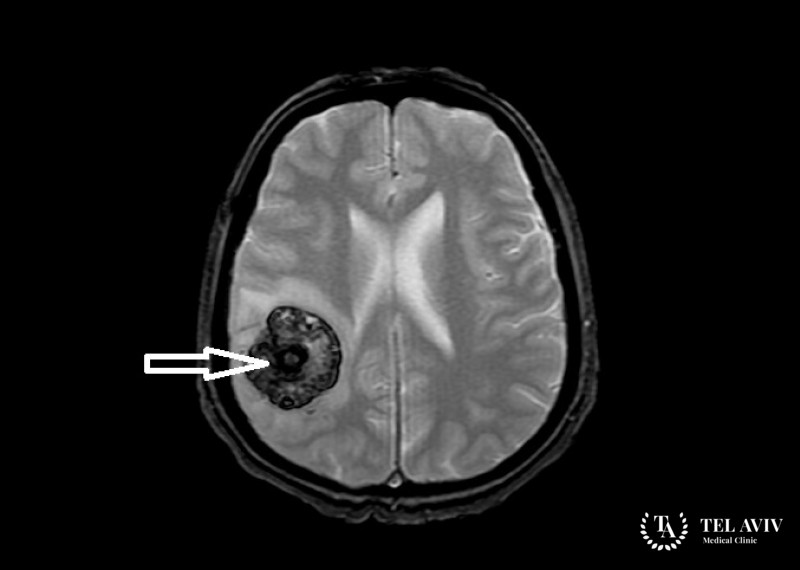

Кавернома головного мозга возникает в кровеносных капиллярах и имеет доброкачественную природу. Несмотря на это, она способна привести к осложнениям, таким как нарушенная функция мозга. Часто обнаруживается кавернозная ангиома случайно, во время проведения исследования. Беря свое начало в сосудах, опухоль может локализоваться в любом участке головного мозга. Из-за местонахождения и редкости заболевания, новообразование не так давно трудно поддавалось обнаружению. Но благодаря прогрессу в сфере визуальной диагностики, распознать сосудистую патологию стало возможным даже на начальных стадиях роста.

- МРТ с контрастом дает изображение даже сгустков небольших размеров.